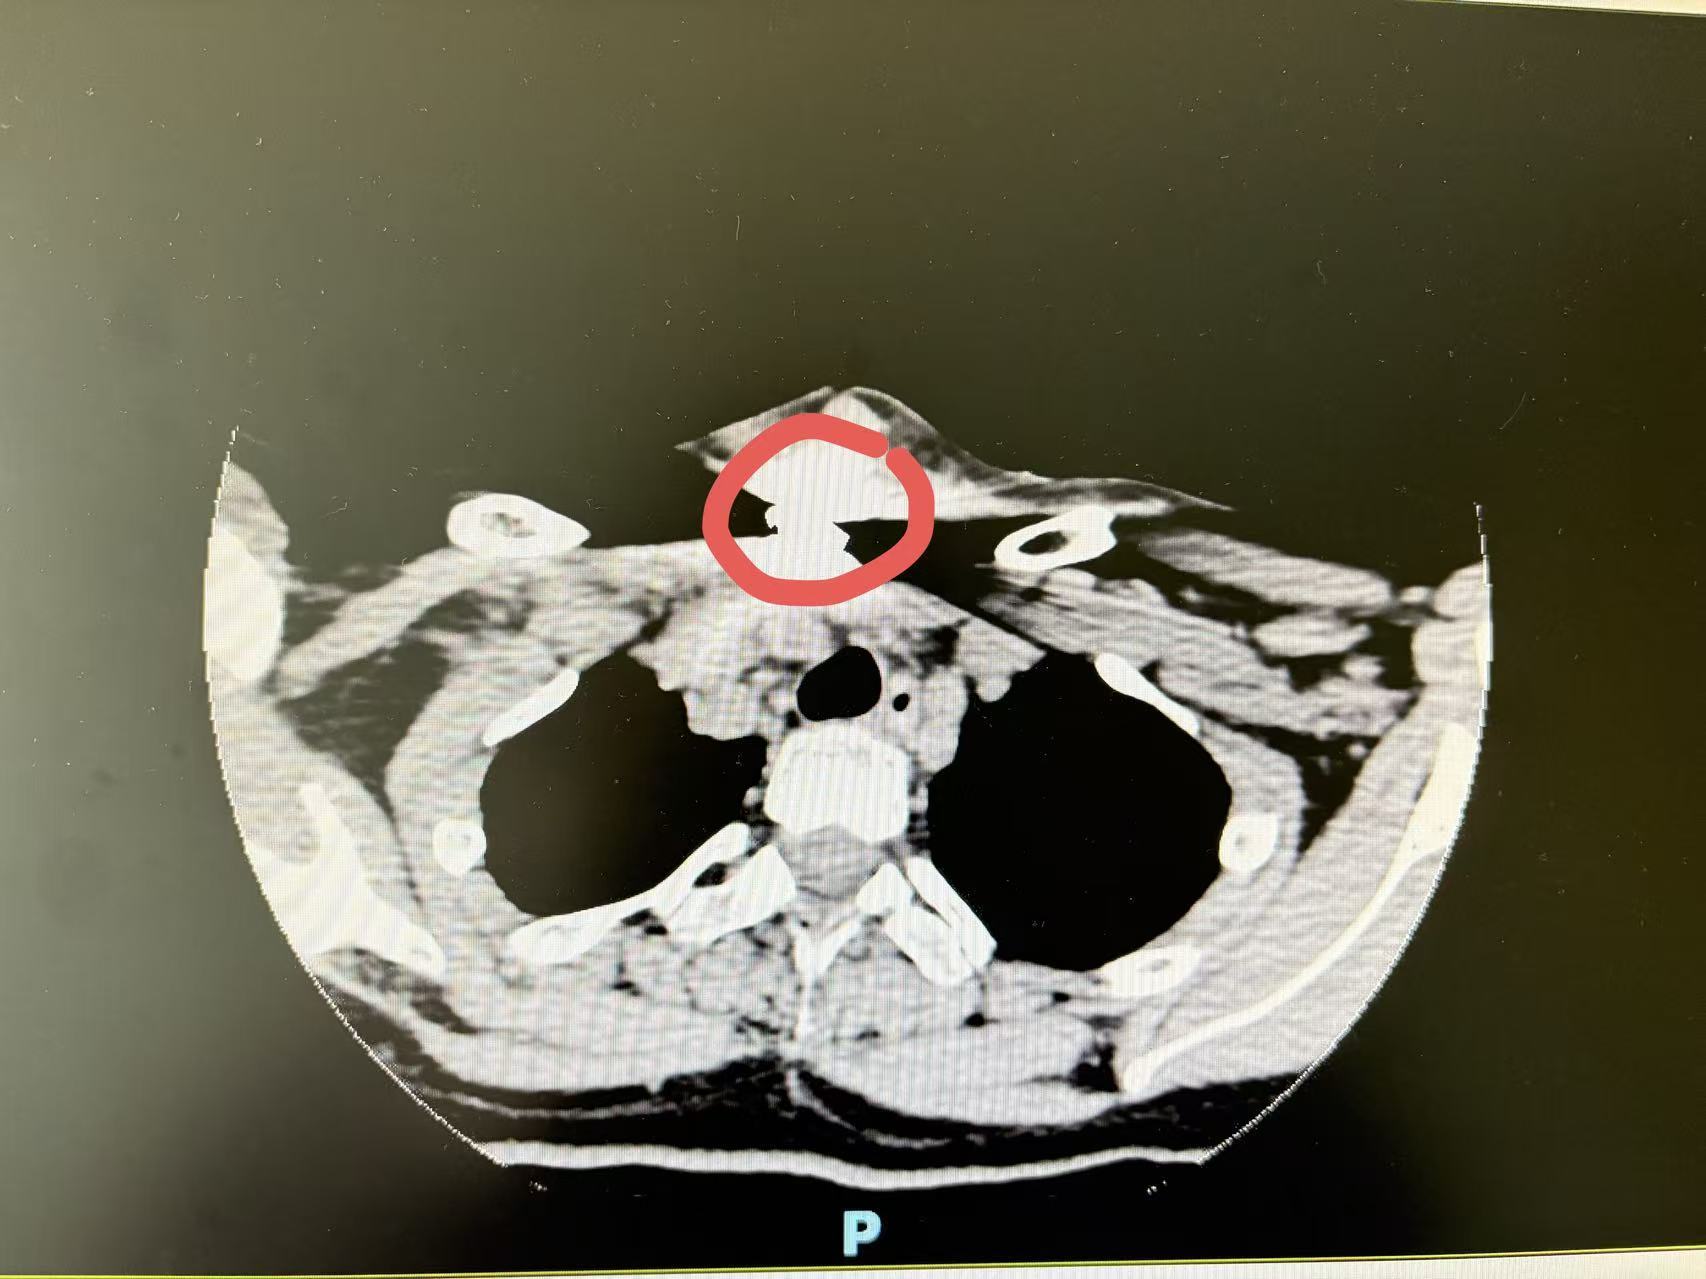

原来,颈部CT显示,这枚大小约1×2cm小小的零件出现在T2-3水平颈根部,周围组织的肿胀和积气,最致命的是它深深嵌入了颈部的“生命禁区”——紧邻大血管、神经和气管,非常危险。

于是,李女士赶紧转到南京,南医大二附院耳鼻喉头颈外科金芳副主任医师接诊了她,立即安排她入院准备接受手术。金芳和她家属解释:“这枚金属异物所处的位置,是颈部最复杂的区域之一,首先位置较深,其次随着患者颈部的活动,异物在体内移位,手术难度非常高。这个区域血管网络密布,异物就像一颗嵌在在‘电线’和‘水管’旁边的‘锈钉’,稍有不慎,就可能引发致命性大出血。除了气管和大血管,还有喉返神经。喉返神经就像支配我们声音的‘电路’,一旦在手术中受损,就会导致术后声音嘶哑,甚至是永久性的。所以,要在‘密林’中取出这颗‘锈钉’并不容易。”